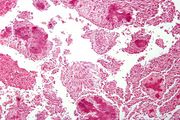

| 04:03, 21 August 2013 | IPLab10Candidiasis7.jpg (file) | 77 KB | This is a low-power photomicrograph of the kidney from this same case. Note the Candida colonies (arrows). The pseudohyphae are evident around the periphery of these colonies even at this low magnification. | 1 | |